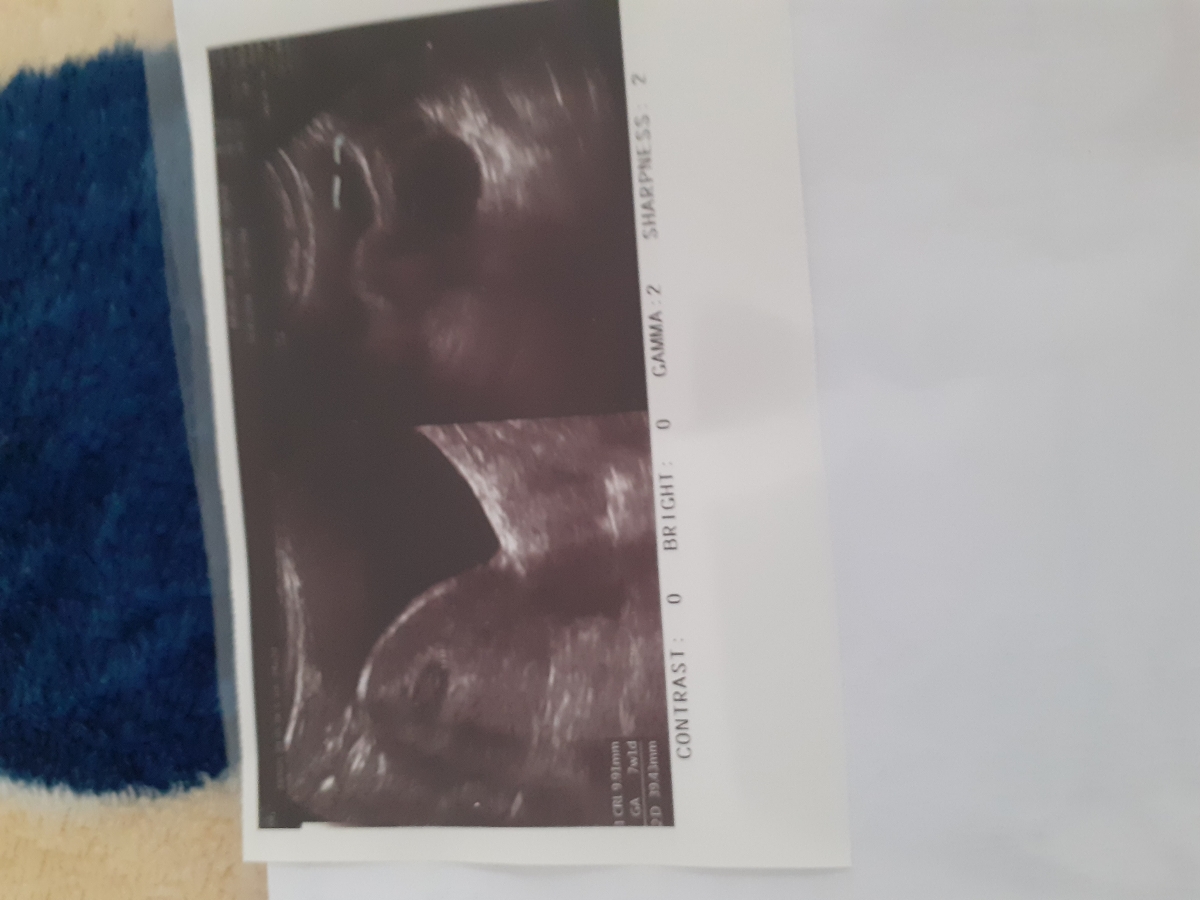

عایا سونوگرافیم همه چی طبیعی است؟

سلام لطفا عکس سونو میذاریم ببینید همه چی طبیعی است...ونزدیکی خطری نداره

مباااارکه🙋♀️😍😍😍 همه چی خوبه

سلام همه موارد نرمال است اما اجازه نزدیکی را باید پزشک معالج بده